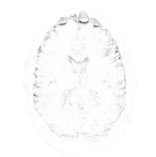

Refer to captionRefer to captionRefer to captioninitializationOptimal TransportRefer to captionRefer to captionRefer to captionOptimal Transport (blurred)Refer to captionRefer to captionRefer to captionMultilevelRefer to captionRefer to captionRefer to captionoptimizedRefer to captionRefer to captionRefer to captionRefer to captionRefer to captionRefer to caption

Figure 6: Example field maps (Subject ID 826353) at initialization (top row) and after optimization with Gauss-Newton (bottom row). The first column uses the proposed optimal transport initialization scheme. The middle column uses the same scheme with an additional Gaussian blur to promote smoothness. The right column uses the coarse-to-fine multilevel initialization scheme from HySCO with five levels, and the final field map is optimized at the original image resolution. The multilevel initialized field map is smooth by construction and further optimized to improve the relative image distance at the full resolution. The optimal transport initialization accurately corrects the distortions but is not smooth in the non-distortion dimensions unless blurred with a Gaussian. After the fine-level optimization all field maps are visually similar.